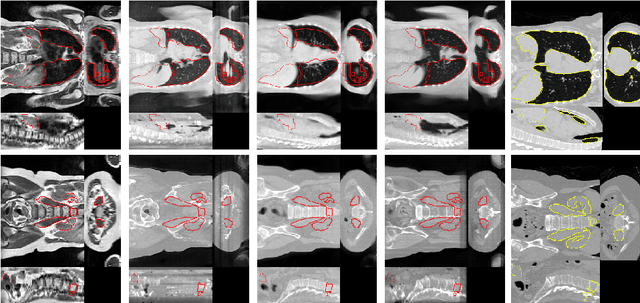

Abstract:Deformable Image Registration (DIR) of MR and CT images is one of the most challenging registration task, due to the inherent structural differences of the modalities and the missing dense ground truth. Recently cycle Generative Adversarial Networks (cycle-GANs) have been used to learn the intensity relationship between these 2 modalities for unpaired brain data. Yet its usefulness for DIR was not assessed. In this study we evaluate the DIR performance for thoracic and abdominal organs after synthesis by cycle-GAN. We show that geometric changes, which differentiate the two populations (e.g. inhale vs. exhale), are readily synthesized as well. This causes substantial problems for any application which relies on spatial correspondences being preserved between the real and the synthesized image (e.g. plan, segmentation, landmark propagation). To alleviate this problem, we investigated reducing the spatial information provided to the discriminator by decreasing the size of its receptive fields. Image synthesis was learned from 17 unpaired subjects per modality. Registration performance was evaluated with respect to manual segmentations of 11 structures for 3 subjects from the VISERAL challenge. State-of-the-art DIR methods based on Normalized Mutual Information (NMI), Modality Independent Neighborhood Descriptor (MIND) and their novel combination achieved a mean segmentation overlap ratio of 76.7, 67.7, 76.9%, respectively. This dropped to 69.1% or less when registering images synthesized by cycle-GAN based on local correlation, due to the poor performance on the thoracic region, where large lung volume changes were synthesized. Performance for the abdominal region was similar to that of CT-MRI NMI registration (77.4 vs. 78.8%) when using 3D synthesizing MRIs (12 slices) and medium sized receptive fields for the discriminator.